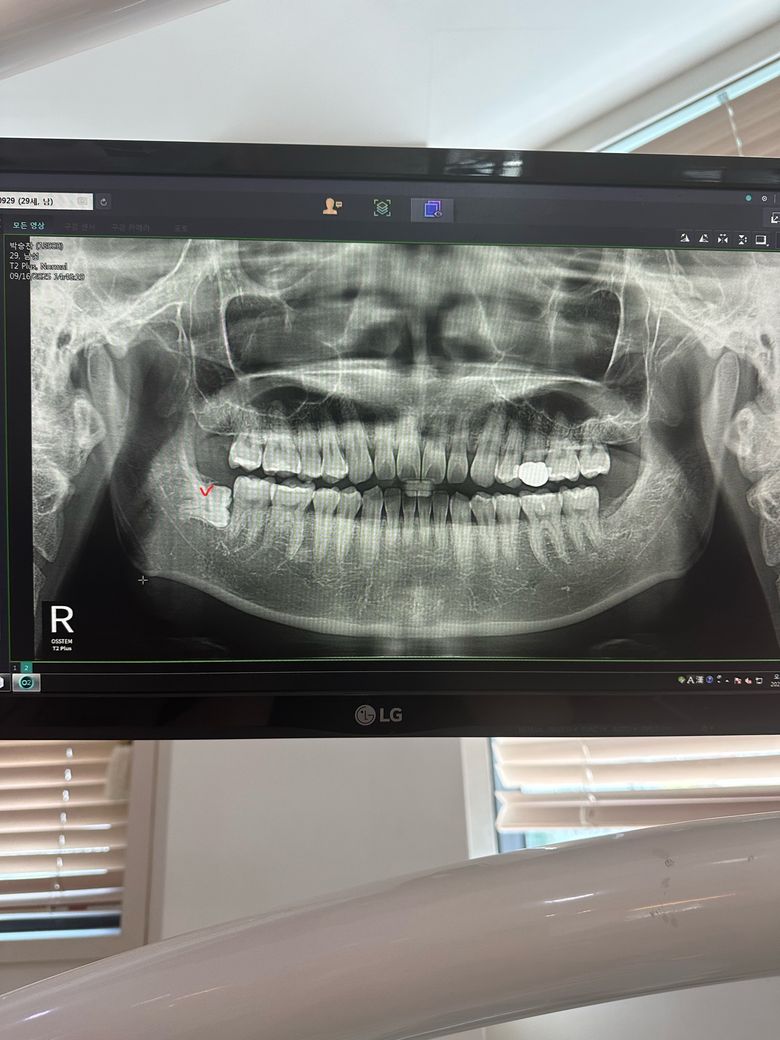

하악 매복사랑니 발치후 잇몸붓기 지속되는경우

완전옆으로 누여있는 사랑니 였고 이틀이후 얼굴에 멍이 올라올정도 였으며

• 1번 째 사진

사랑니의 매복된 정도를 봤을 때 뼈 삭제량도 많았을 것이라 붓기나 통증이 더 오래갈 것 같습니다.

사랑니 매복이 깊어서 잇몸 절개도 많이 햇고, 잇몸뼈 삭제를 많이 한경우에는 붓기가 몇일갈수도 있습니다.